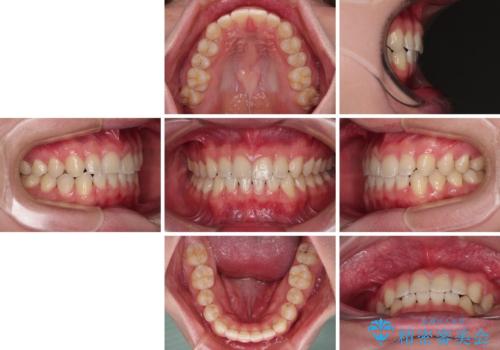

隙間とデコボコを治したい ワイヤー装置による矯正治療

- 前歯のデコボコと隙間を気にして来院された患者様です。

舌の突出癖がなかなか改善されず、治療開始時よりも隙間が大きく開いてしまう時期がありましたが、最終的にしっかりと閉じて終了することができました。